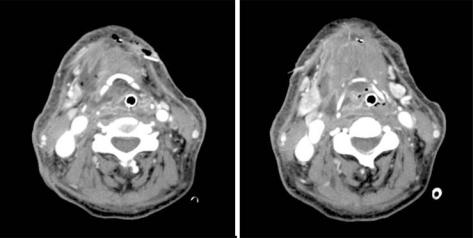

The advent and wide use of antibiotics have decreased the incidence of deep neck infection. When a deep neck infection does occur, however, it can be the cause of significant morbidity and death, resulting in airway obstruction, mediastinitis, pericarditis, epidural abscesses, and major vessel erosion. In our clinic, a patient with diffuse chronic osteomyelitis of mandible and fascial space abscess and necrotic fasciitis due to odontogenic infection at the time of first visit came. We successfully treated the patient by early diagnosis using contrast-enhanced CT and follow up dressing through the appropriate use of radiographic images.